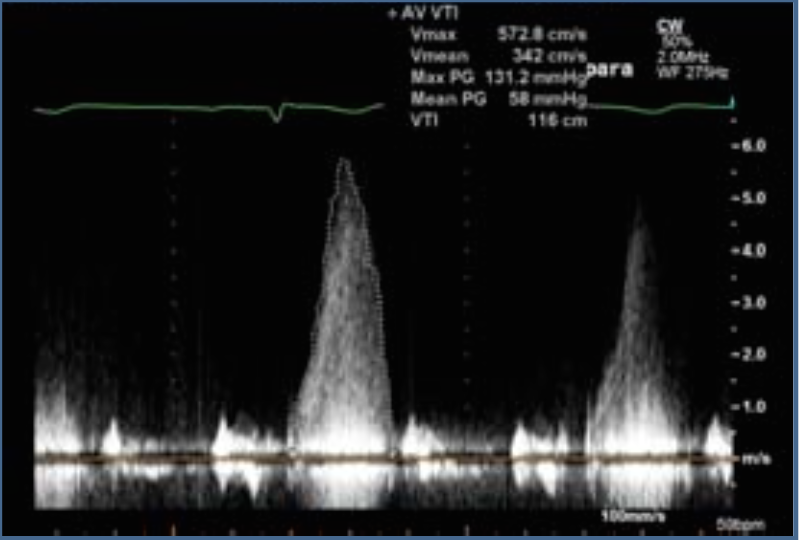

AVA, Mean Grad, velocity associated with severe AS?

<1cm2

>40

>4m/s

Diagnosis across LVOT

HCM